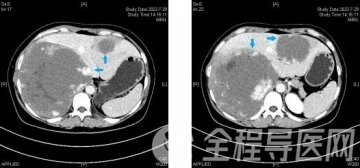

患者张大爷,81岁,有冠心病病史。20天前因“声音嘶哑5月,间断咯血伴憋喘1月,到徐医附院呼吸与危重症医学科呼吸重症监护病房治疗。入院胸部CT检查发现胸廓入口平面纵隔占位,突入气管,造成气管狭窄,如不及时解决气管狭窄问题,随时可能出现窒息,危及生命。呼吸与危重症医学科陈碧主任组织内镜团队会诊后,考虑到患者肿瘤已侵犯大气道,建议行气管支架植入缓解呼吸困难,从而为基础疾病的治疗争取时间。由于张大爷气管狭窄位置较高,且存在冠心病(两次置入冠脉支架),心力衰竭,植入气管支架难度大、风险高。患者家属犹豫再三后要求转至肿瘤科继续姑息治疗。但患者转出ICU后病情有进一步加重的趋势,情况危机,命悬一线。经过孙理想医师耐心解释呼吸内镜治疗的优点和特点,让患者家属坚定了进行呼吸内镜治疗的信心。